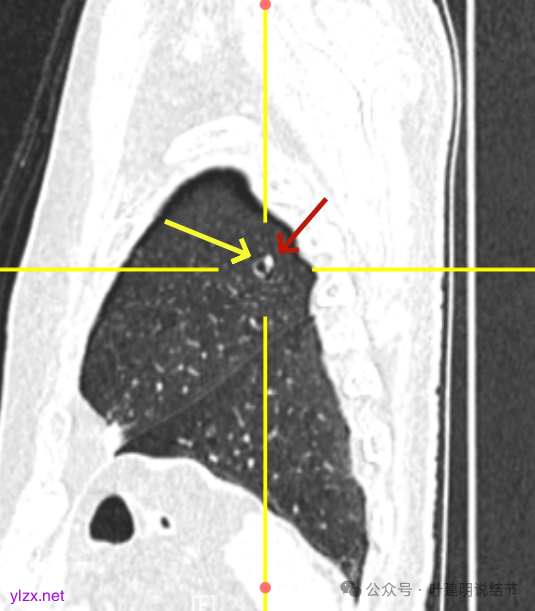

矢状位见病灶囊壁有结节状高密度。

右下叶也有囊腔灶。